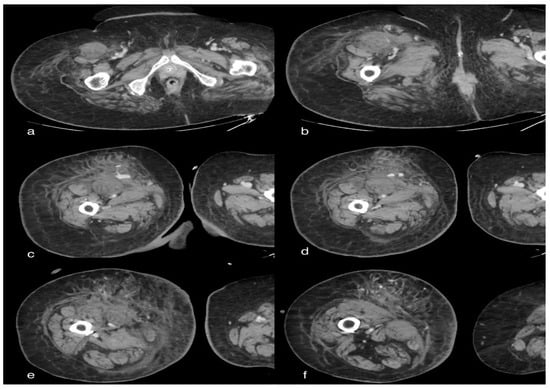

A total-body CT scan was performed after the intravenous administration of a contrast medium under a specific study protocol to assess the aorta and vessels of the lower limb conditions, for the patient’s clinical condition and the elevated D-dimer. The CT scan demonstrated opacification of the left common iliac artery and a filiform left superficial femoral artery. Reduced opacification of the left femoral vein was observed at a later stage of the research. Moreover, a peripheral hypodense flap of both kidneys was observed during the contrast phases, likely as a result of renal cortical necrosis. In addition, a small area of necrotic hypoperfusion, which was located at the upper pole of the spleen, was observed as well. Furthermore, diffuse ground-glass opacity (GGO) can be observed on CT imaging of the lungs, associated with crazy-paving patterns. The total severity score was 18/20 s (according to Chung et al.) [12] (Figure 1).

Figure 1. Axial sections of the abdomen in the basal (a) and arterial (b) phases; the arrows show a small hypo-dense subcapsular area well delimited by the splenic capsule. This area in the arterial phase remains as a hypodense lesion. Lack of enhancement. Axial section of the abdomen in the arterial (c) and portal venous (d) phases; the arrows show a non-enhancing renal cortex. Images show a normal enhancing renal medulla (acute cortical necrosis), and the hypodense cortex is surrounded by a thin peripheral rim of enhancement in the portal venous phase.

Concerning renal cortical necrosis, contrast-enhanced CT demonstrates a non-enhancing renal cortex and a normal enhancing renal medulla (reverse rim sign) [18]. CT performed during the portal venous phase represents the imaging exam of choice for spleen infarction and typically demonstrates, in the case of peripheral infarction, a wedge-shaped hypo-enhancing region [19].